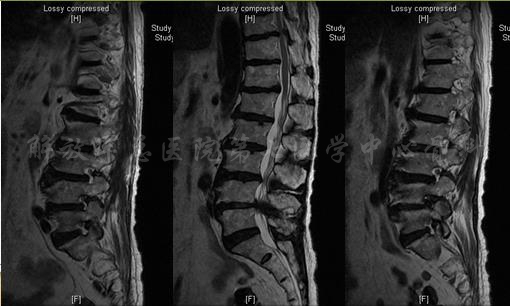

MRI

MRI颈4-5(左)、颈5-6(中)颈6-7(右)

矢状位MRI

轴位MRI:腰3-4(左)、腰4-5(中)、腰5骶1(右)